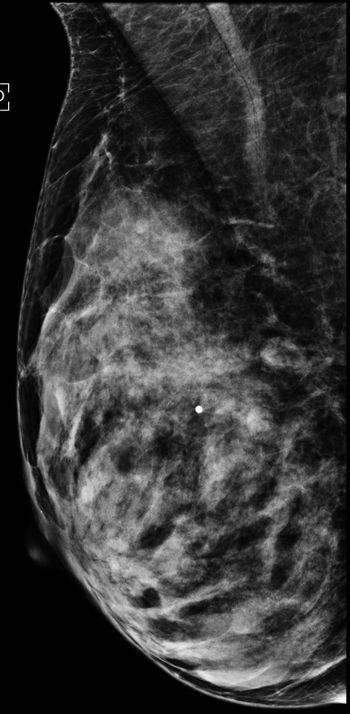

A 72 year-old woman presents for routine screening mammogram with no complaints.

Screening ultrasounds plus mammography may find more cancers in women who have breast dense tissue.

Tomosynthesis, photon counting and photoacoustic imaging are just a few of the growing options for breast imaging technology.

Fewer ultrasounds and biopsies were seen for women referred for breast tomosynthesis after recall for focal asymmetric density following screening mammography.